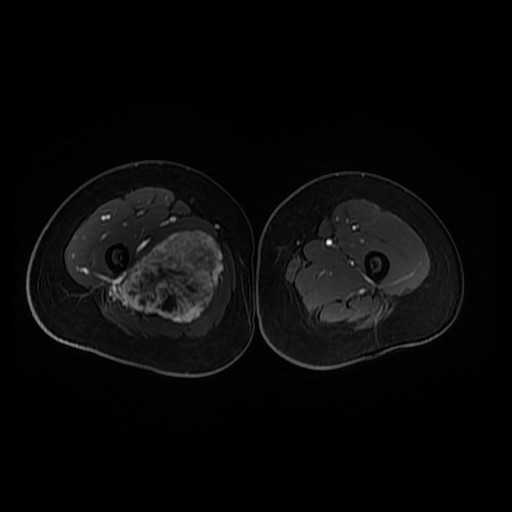

诊断:肺占位性病变(转移瘤?);大腿软组织疾患(右侧大腿肿物) 治疗:入院右下肢MR平扫+增强扫描:右侧大收肌软组织占位性病变,考虑间叶源性恶性肿瘤可能性大,血管源性可能?瘤周多发静脉曲张及侧枝循环形成,建议CT增强扫描进一步检查明确血管情况。遂于声引导下右大腿肿物穿刺活检,病理结果提示:(右大腿肿物)送检穿刺组织,肿瘤细胞形成器官样及腺泡状结构,细胞巢间为纤维性分隔,细胞呈大圆形、多边形,胞质丰富透亮,部分呈嗜伊红色,细胞核大,核分裂象少见,结合临床病史及免疫组化,考虑为腺泡状软组织肉瘤。免疫组化结果(①):CK(-),Vim(-),Ki-67(5%+),HMB45(-),MelanA(-),SMA(+),desmin(-),Myogenin(-),MyoD1(-),S100(-),NSE(部分+),CD56(-)。